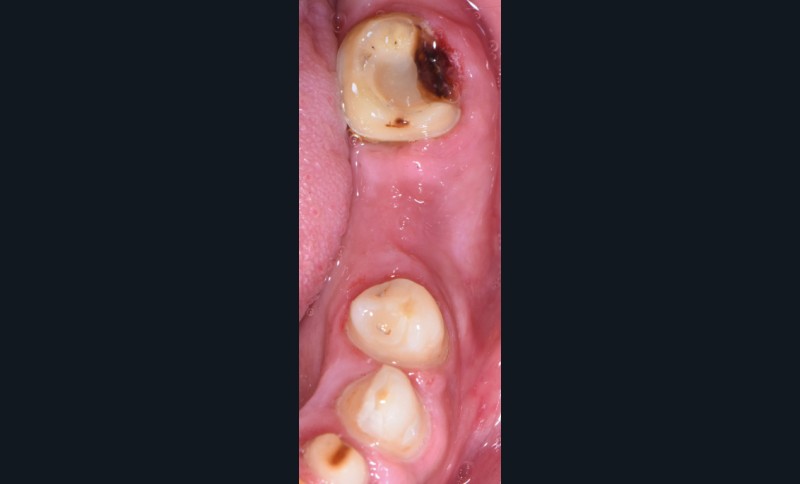

Au vu du contexte para-fonctionnel et de l’étendue de la perte tissulaire, des coiffes périphériques minimalement invasives ont été choisies afin de restaurer l’esthétique et la fonction. Actuellement, aucun consensus n’est fait sur le choix du matériau d’infrastructure à privilégier. Les matériaux hybrides usinables présentent des propriétés mécaniques, physiques et biologiques intéressantes en contexte d’usure sévère (e.g., module d’élasticité, résistance à la propagation de fêlures, facilité de réintervention). Une réhabilitation globale avec remontée de dimension verticale d’occlusion (DVO) par l’intermédiaire de coiffes composites renforcés en nano-céramiques est décrite.